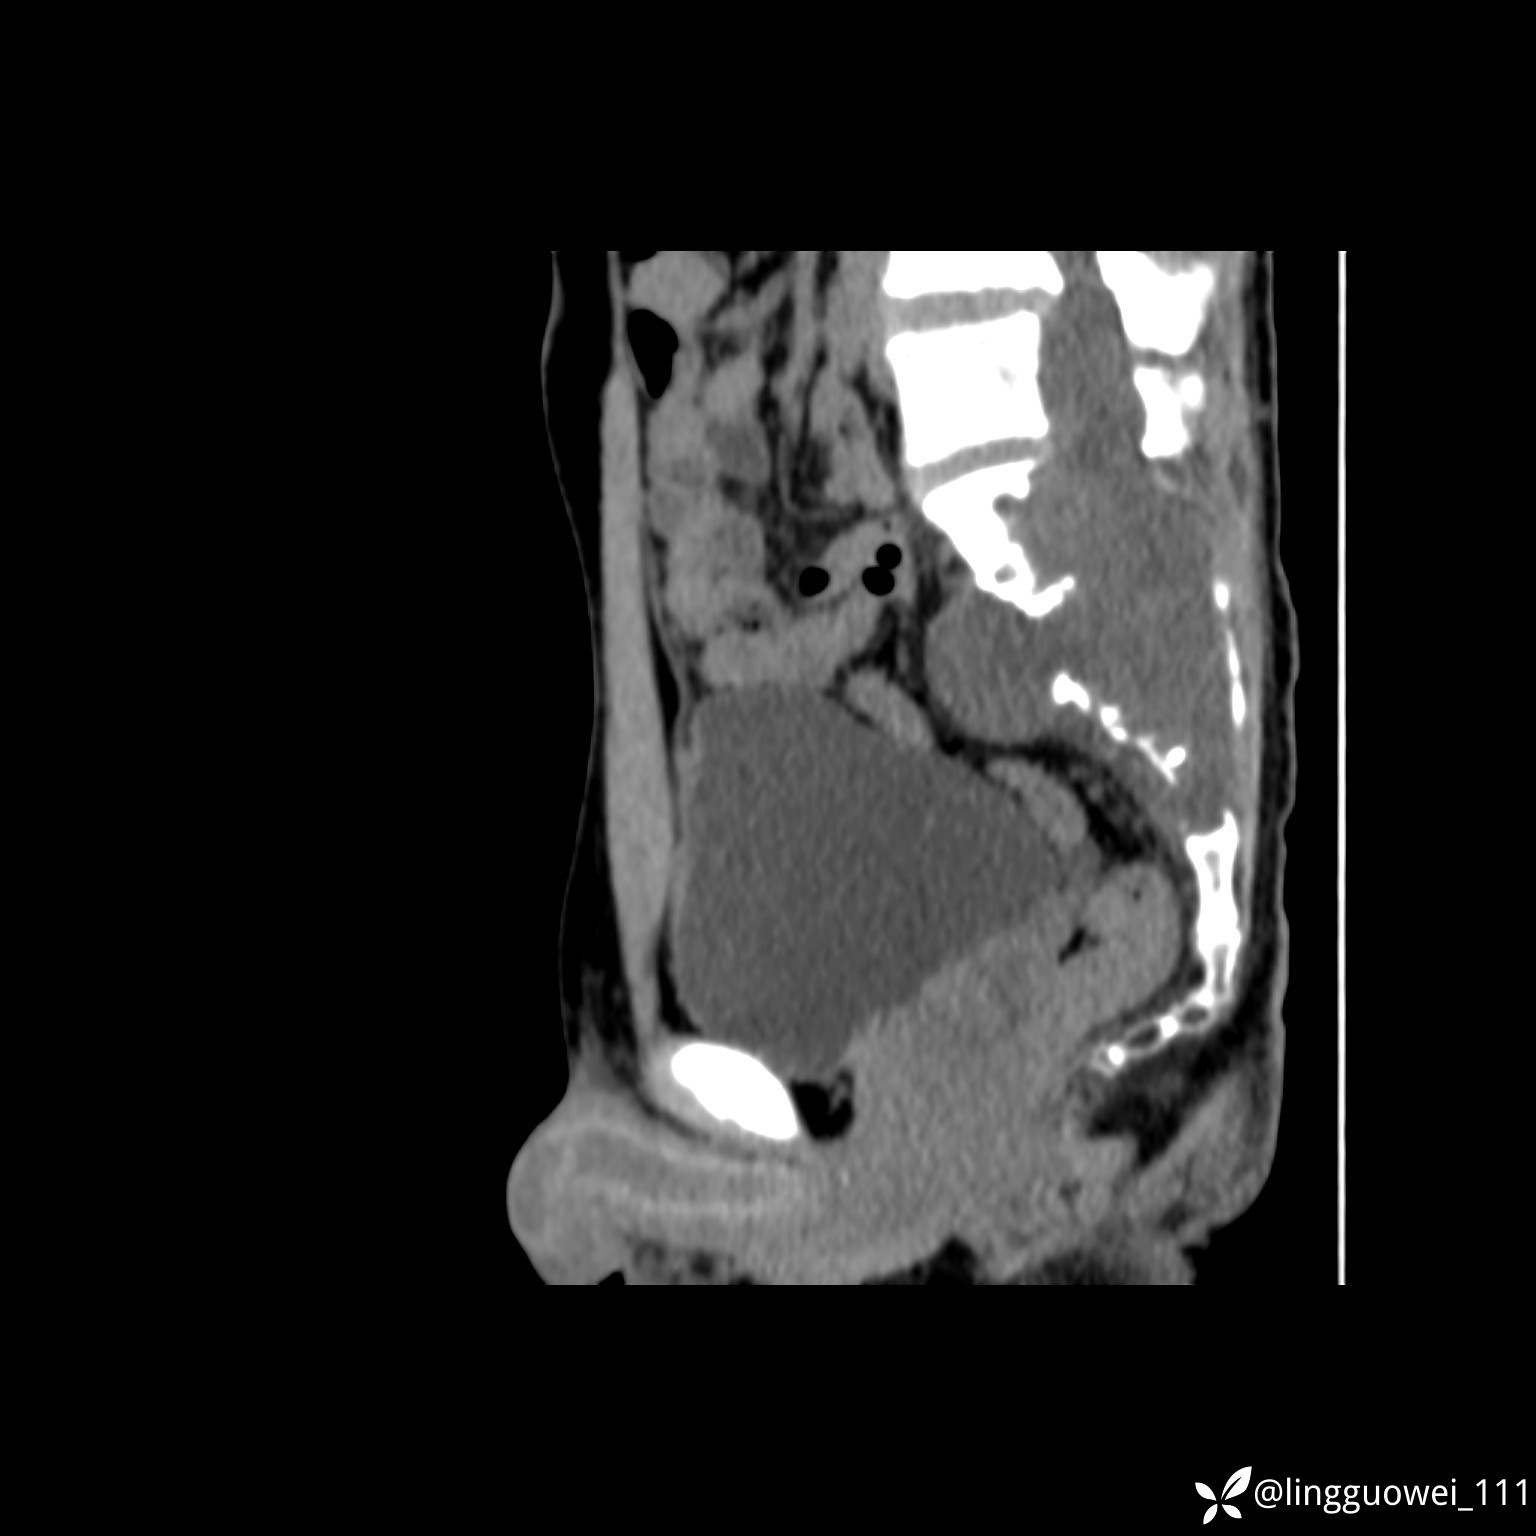

男,25岁,腰痛4年,加重左下肢痛5天,先上传X光片,第2天再上传CT。MR

动脉期:

MR:(忘记截图常规序列,不过应该不影响诊断)